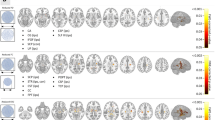

The aim of this study was to assess the MR imaging findings of transneuronal degeneration of limbic system in the patients with temporal lobe epilepsy, and to detect the influence of surgery on the anatomy of the limbic system. Axial and coronal T1- and T2-weighted MR images were retrospectively analyzed in 34 patients with temporal lobe epilepsy, focusing on transneuronal degeneration. In 17 of the 34 patients, MR images were also analyzed after selective amygdalo-hippocampectomy. Atrophy of the fornix, mamillary body, mamillothalamic tract (MTT), and thalamus ipsilateral to the epileptic focus was demonstrated on MR images in 14.7, 17.6, 8.8, and 11.8% of the 34 patients, respectively. Focal hyperintensity of the thalamus was found on T2-weighted images in 8.8% of the 34 patients. In 17 patients who were evaluated before and after surgery, transneuronal degeneration was seen more frequently after surgery: fornix (11.8 vs 29.4%), mamillary body (11.8 vs 52.9%), MTT (5.9 vs 11.8%), and thalamus (11.8 vs 11.8%). Transneuronal degeneration of the limbic system is clearly demonstrated by MR imaging in patients with temporal lobe epilepsy, and surgical intervention induces transneuronal degeneration more frequently.

Abnormal findings of the limbic system outside the hippocampus on MR images were revealed in 11 (32.4%) of the 34 patients. Table 1 reveals the MR imaging data on each structure composing the limbic system. In 15 (44.1%) of the 34 patients, there was a small hippocampus ipsilateral to the epileptic focus. The signal intensity of the hippocampus was increased on T2-weighted images in 7 patients (20.6%). In only 1 (2.9%) of the 34 patients was it found in contralateral side of the epileptic focus. Atrophy of the fornix ipsilateral to the epileptic focus was found in 5 (14.7%) of the 34 patients. Only one (2.9%) of all the patients, who had a cavernous hemangioma, showed atrophy of the fornix on the contralateral side. Atrophy of the mamillary body ipsilateral to the epileptic focus was found in 6 (17.6%) of all the patients. Only one patient (2.9%), the same patient with a cavernous hemangioma, had contralateral atrophy of the mamillary body. Atrophy of the MTT ipsilateral to the epileptic focus was found in 3 (8.8%). Atrophy of the thalamus was also found in 3 (8.8%). Atrophy of the MTT and thalamus was not seen on the contralateral side. A focal increase of the signal intensity in the thalamus on T2-weighted images was found in 3 (8.8%) of the 34 patients, but no such increase was identified in the fornix, mamillary body, or MTT.

When evaluation was limited to the 15 patients with hippocampal sclerosis on MR images, the frequency of atrophy in the limbic system increased as follows: atrophy of the fornix in 4 (26.7%); of the mamillary body in 4 (26.7%); of the MTT in 2 (13.3%); and of the thalamus in 3 (20%; Table 2). The frequency of the atrophy of fornix and thalamus was significantly higher in the patients with hippocampal sclerosis than those without hippocampal sclerosis on MR imaging.

When comparing the prevalence of the findings before and after surgery in the 17 patients who underwent surgery, the frequency of limbic system atrophy tended to be higher after surgery than before surgery (Table 3). Limbic system atrophy ipsilateral to the epileptic focus was found in the following structures after the surgery: 5 (29.4%) in the fornix (Fig. 1); 9 (52.9%) in the mamillary body; 2 (11.8%) in the MTT (Fig. 2); and 2 (11.8%) in the thalamus. The frequency of mamillary body atrophy was significantly higher after surgery than before surgery (p=0.015), but there was no significant difference for the other structures.

Previous reports have shown asymmetrical fornix and mamillary body in 20–50% of temporal lobe epilepsy patients on MR images [13, 14, 16]. In those reports, all the patients were intractable temporal lobe epilepsy patients with histologically proven hippocampal sclerosis. In comparison with such reports, the frequency of fornix and mamillary body asymmetry was lower (14.7 and 17.6%, respectively) in our study. This difference may be mainly related to patient selection. Because we retrospectively reviewed temporal lobe epilepsy patients who were consecutively examined by MR imaging, this study included various grade of epilepsy from intractable cases with hippocampal sclerosis undergoing surgery to mild cases with no MR abnormalities. When evaluation was limited to the patients with hippocampal sclerosis confirmed on MR imaging, the frequency of fornix and mamillary body asymmetry increased to 26.7%. This datum is similar to the result reported by Kim et al., who reported that asymmetrically small fornix was shown in 39% of cases [16].

Our data compared between before and after surgery proved that the more severe neuronal damages are, the more limbic system atrophy occurs. The frequency of limbic system atrophy was higher (11.8–52.9%) after surgery than before surgery (5.9–11.8%). Kim et al. reported the same result compared between presurgical and postsurgical groups, which described that the frequency of asymmetrical small fornix and mamillary bodies increased more than twice after surgery [16]; thus, the neuronal damage caused by surgery probably interrupted efferent axonal activity, resulting in atrophic change of the entire limbic system. Although a significant difference was found only for the mamillary body in our study, further investigations are warranted to achieve a careful assessment of other structures in a larger number of cases. On the other hand, there was no correlation between the time interval from the onset of epilepsy and atrophy of each structure in the limbic system. Some of the previous reports reveal that the time interval might correlate with the abnormal MR findings, but Oikawa et al. reported that the extent of the abnormality of the limbic system did not correlate with time interval [20]. This is because the length of the history does not always indicate the clinical severity. To evaluate the clinical severity precisely, we need another appropriate indicator including not only the length of the history, but also severity of the epilepsy itself.

To our knowledge, most previous studies evaluated the mamillary body and the fornix, and evaluation of transneuronal degeneration of the MTT and thalamus has only been performed in a few previous studies [15]. Kataoka et al. [3] demonstrated one case of abnormal appearance of the MTT and mamillary body on MR images in patient with simple and complex partial seizures. In this study, we found atrophy of the MTT and thalamus in 8.8% of the patients. Its frequency was lower than that of atrophy of the fornix and mamillary body, suggesting that structures directly connected to the hippocampus might be more influenced by abnormal electrical activity than those indirectly connected.